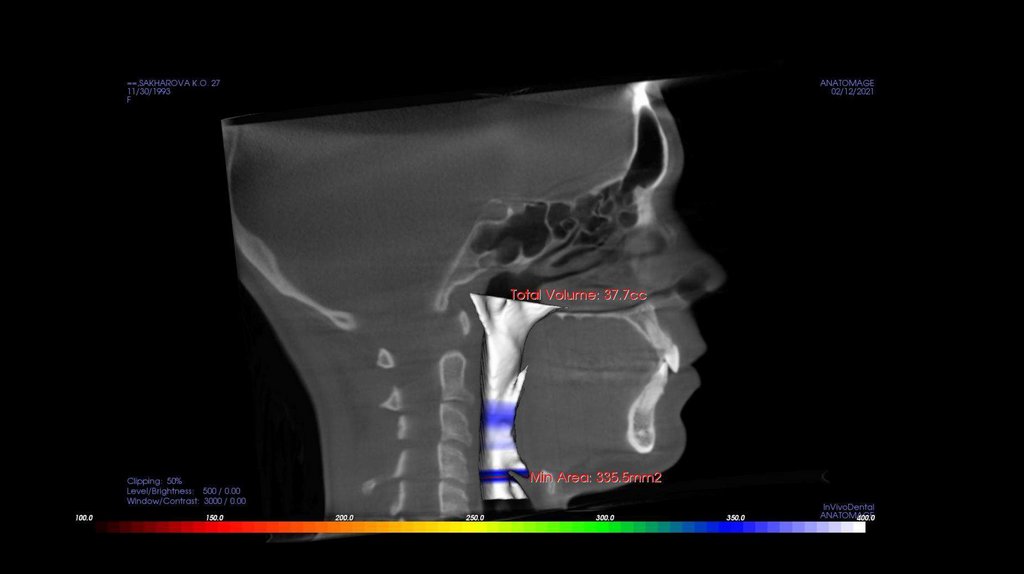

По рассчетам снимков:

• Ретрузия резцов верхней челюсти

• Компрессия головок суставов, особенно правого( началось

ремоделирование)

• Костная ассиметрия(10 мм)

• 2 класс

• 25, 46 зуб – нуждается в санации

• Требуется профессиональняа гигиена полости рта

• Клиновидные дефекты 43, 44

• 18, 28, 38, 48 отсутствуют.